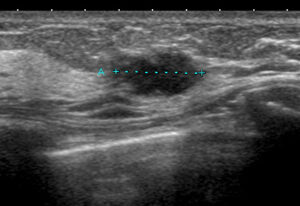

Aクリニック 初診時US ①

これを自信たっぷり「大丈夫だ、線維腺腫」っていったわけ?

このエコー見たとき、おったまげた(昭和?)よ!

とても画像だけで「線維腺腫と言い切れるレベル=きれいな楕円形」ではないよね??